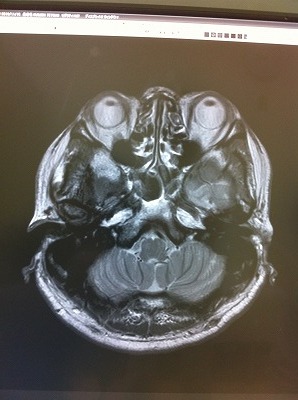

頭のてっぺんから、喉元辺りまで撮影したということで何枚か写真を見た中で、もっともグロテスク?面白い写真がこれですね。

ちょうど、目の高さを輪切りにしたものですから、、上に、目、鼻、、左右の空洞が耳、、その他はなんでしょうね?

で、先生が、この写真を見ながら、、

「ちょっと気になる点があるんですよね。。。。」

「やっぱり、、、なにもないはずがない。。。」

「写真で言う所の、左上に、白い島のようなものが見えますよね。。。」

確かに、、ありますね。。。

「その部分は、脳が死んでいる所です」 「小梗塞、もしくはラクナ梗塞といいます」

※ラクナ梗塞(小梗塞)

脳の細い血管が詰まって起こる脳梗塞

脳に入った太い血管は、次第に細い血管へと枝分かれしていきます。ラクナ梗塞はこの細かい血管が高血圧による血管変性や動脈硬化が原因で狭くなり、詰まることによって起きます。脳の血管の閉塞により、脳の組織の一部が死んで脱落し空洞を残すためにラクナ(小さなくぼみ)梗塞と呼ばれています。日本人に最も多いタイプの脳梗塞です。

※症状

小さな脳梗塞ですが運動障害や感覚障害、言語障害を起こすことがあります。こうした場合は通常の脳梗塞と同じような治療が必要になります。

また症状がはっきりしない場合は無症候性と言いますが、再発により神経症状が出現する率が高くなってしまうのと、再発を繰り返すことで認知症の原因になってしまうのでラクナ梗塞の再発を予防(高血圧、糖尿病、高脂血症といった動脈硬化の危険因子の改善)していくことが、治療の方法となります。

ん。。。。。「今すぐ治療の必要はないですが、煙草や食生活には充分注意してください。」 はい。。

「食生活で、改善できるのですか?」

「死んでいますから、改善はしません。進行を止める。遅らせる事は出来ます」

「60歳を過ぎると、この程度は普通です。ちょっと早いね。」